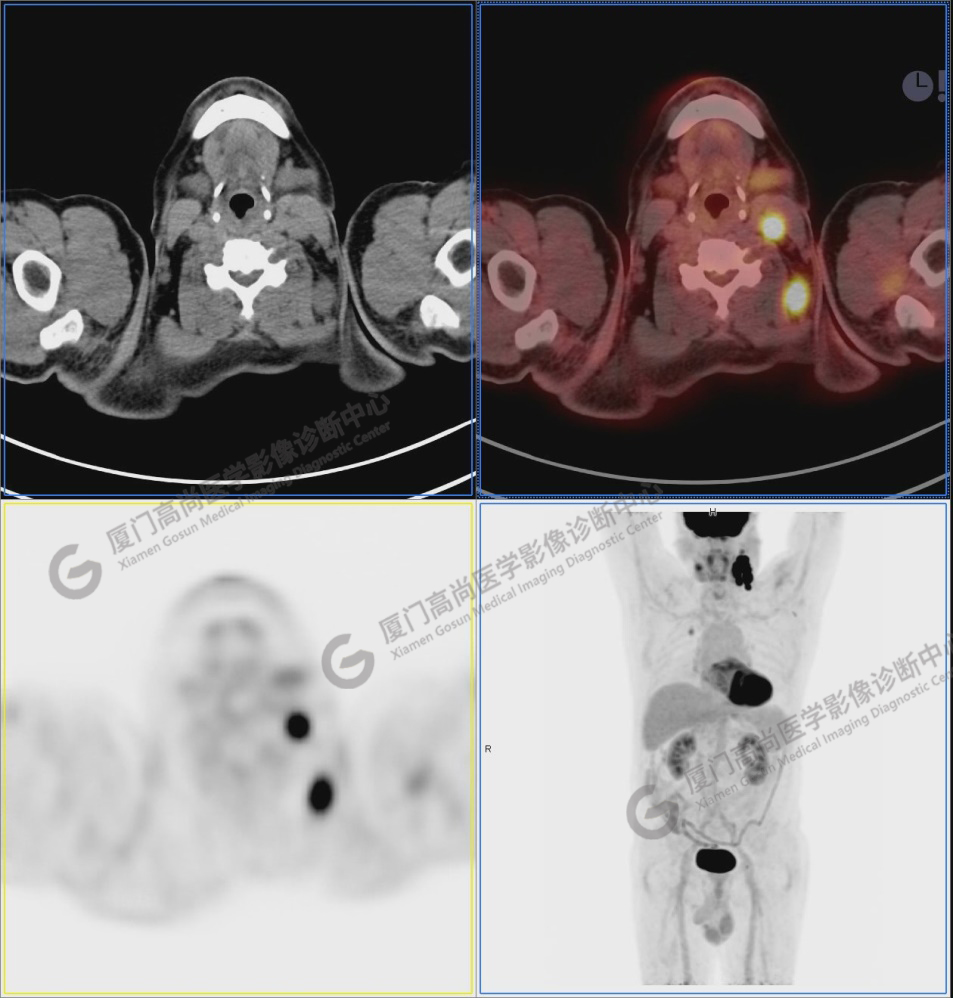

L女士,59歲,發(fā)現(xiàn)左頸部淋巴結(jié)腫大伴疼痛1月余,吞咽不適20余天。左鎖骨上淋巴結(jié)穿刺活檢:轉(zhuǎn)移性鱗狀細胞癌。彩超發(fā)現(xiàn)甲狀腺左葉實性結(jié)節(jié)(4a類),予以細針穿刺:可供診斷上皮細胞量不足,樣本不滿意。既往史無殊,無吸煙、飲酒嗜好,無家族腫瘤史。

圖1:PET/CT全身圖像

圖2-9:雙側(cè)鎖骨區(qū)、縱隔、右側(cè)內(nèi)乳區(qū)、腸系膜緣、腹膜后、雙側(cè)髂血管旁及盆腔多發(fā)腫大淋巴結(jié)影,代謝不同程度增高,考慮為轉(zhuǎn)移。